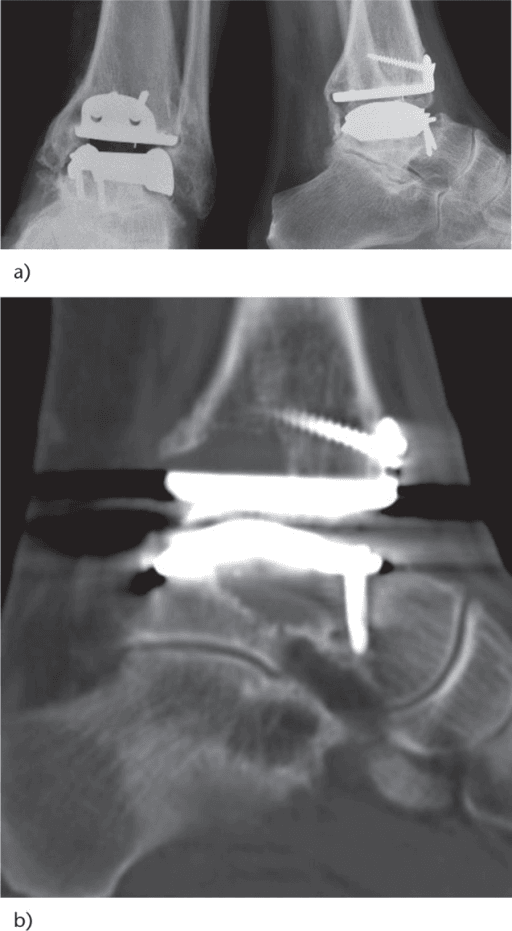

Why WBCT Helps the Syndesmosis

| Problem | What WBCT adds | Clinical use |

|---|---|---|

| Subtle instability | Shows widening or fibular malposition under load | Diagnose occult instability |

| Post-fixation assessment | Quantifies residual diastasis or rotational malreduction | Check reduction quality |

| Equivocal radiographs | Provides bilateral cross-sectional comparison | Resolve borderline cases |

High-Yield Point